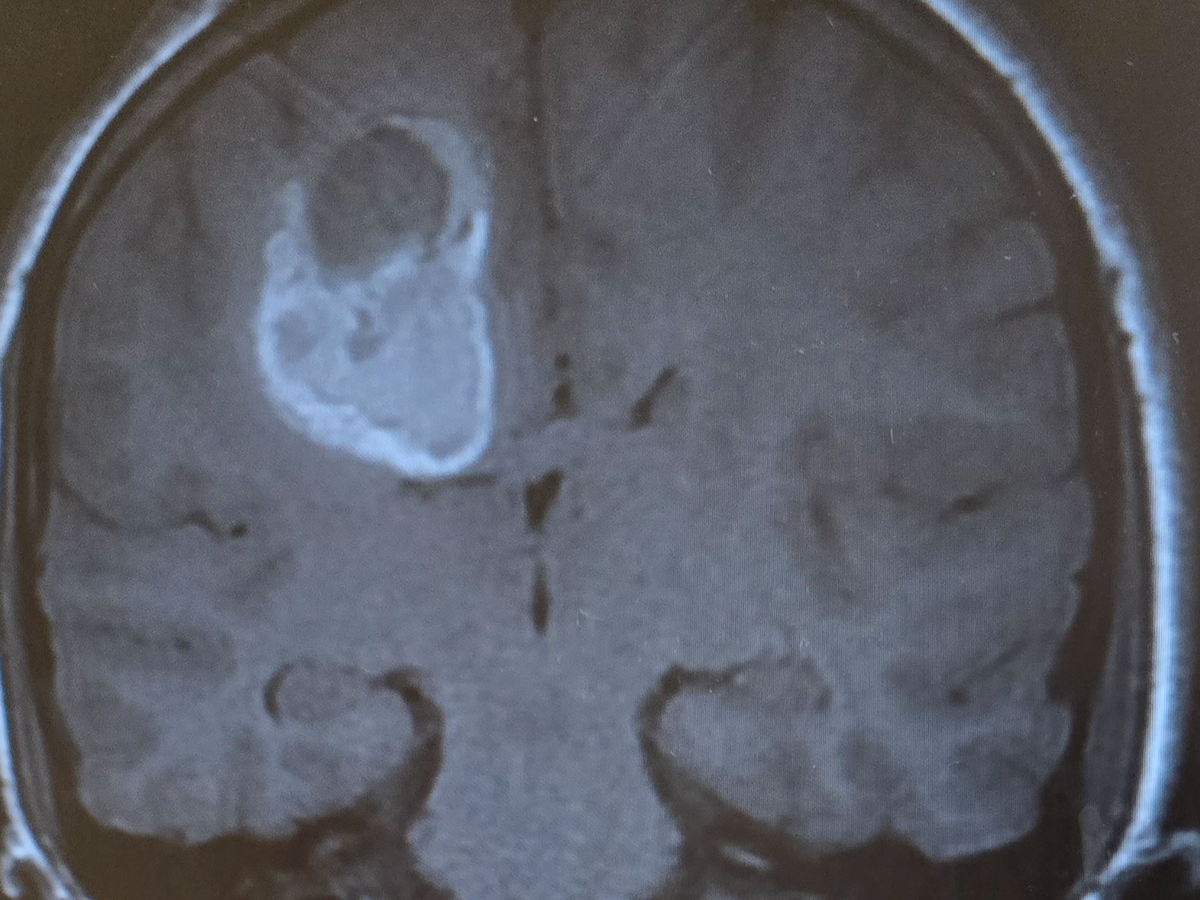

Our world has been turned upside down. Our 13-year-old son, Mason, has recently been diagnosed with a very large 4.3 cm mass in his brain with significant swelling that has hemorrhaged and is now facing brain surgery on January 7th.

No child should ever have to endure something like this, and no parent should have to watch their child go through this. Within a week's time span, Mason lost all movement and control of the left side of his body. He was rushed to multiple doctors before finally getting some answers. He has a Cavernoma. It is an abnormal cluster of blood vessels with slow-flowing blood. This is what causes the neurological symptoms he is having.